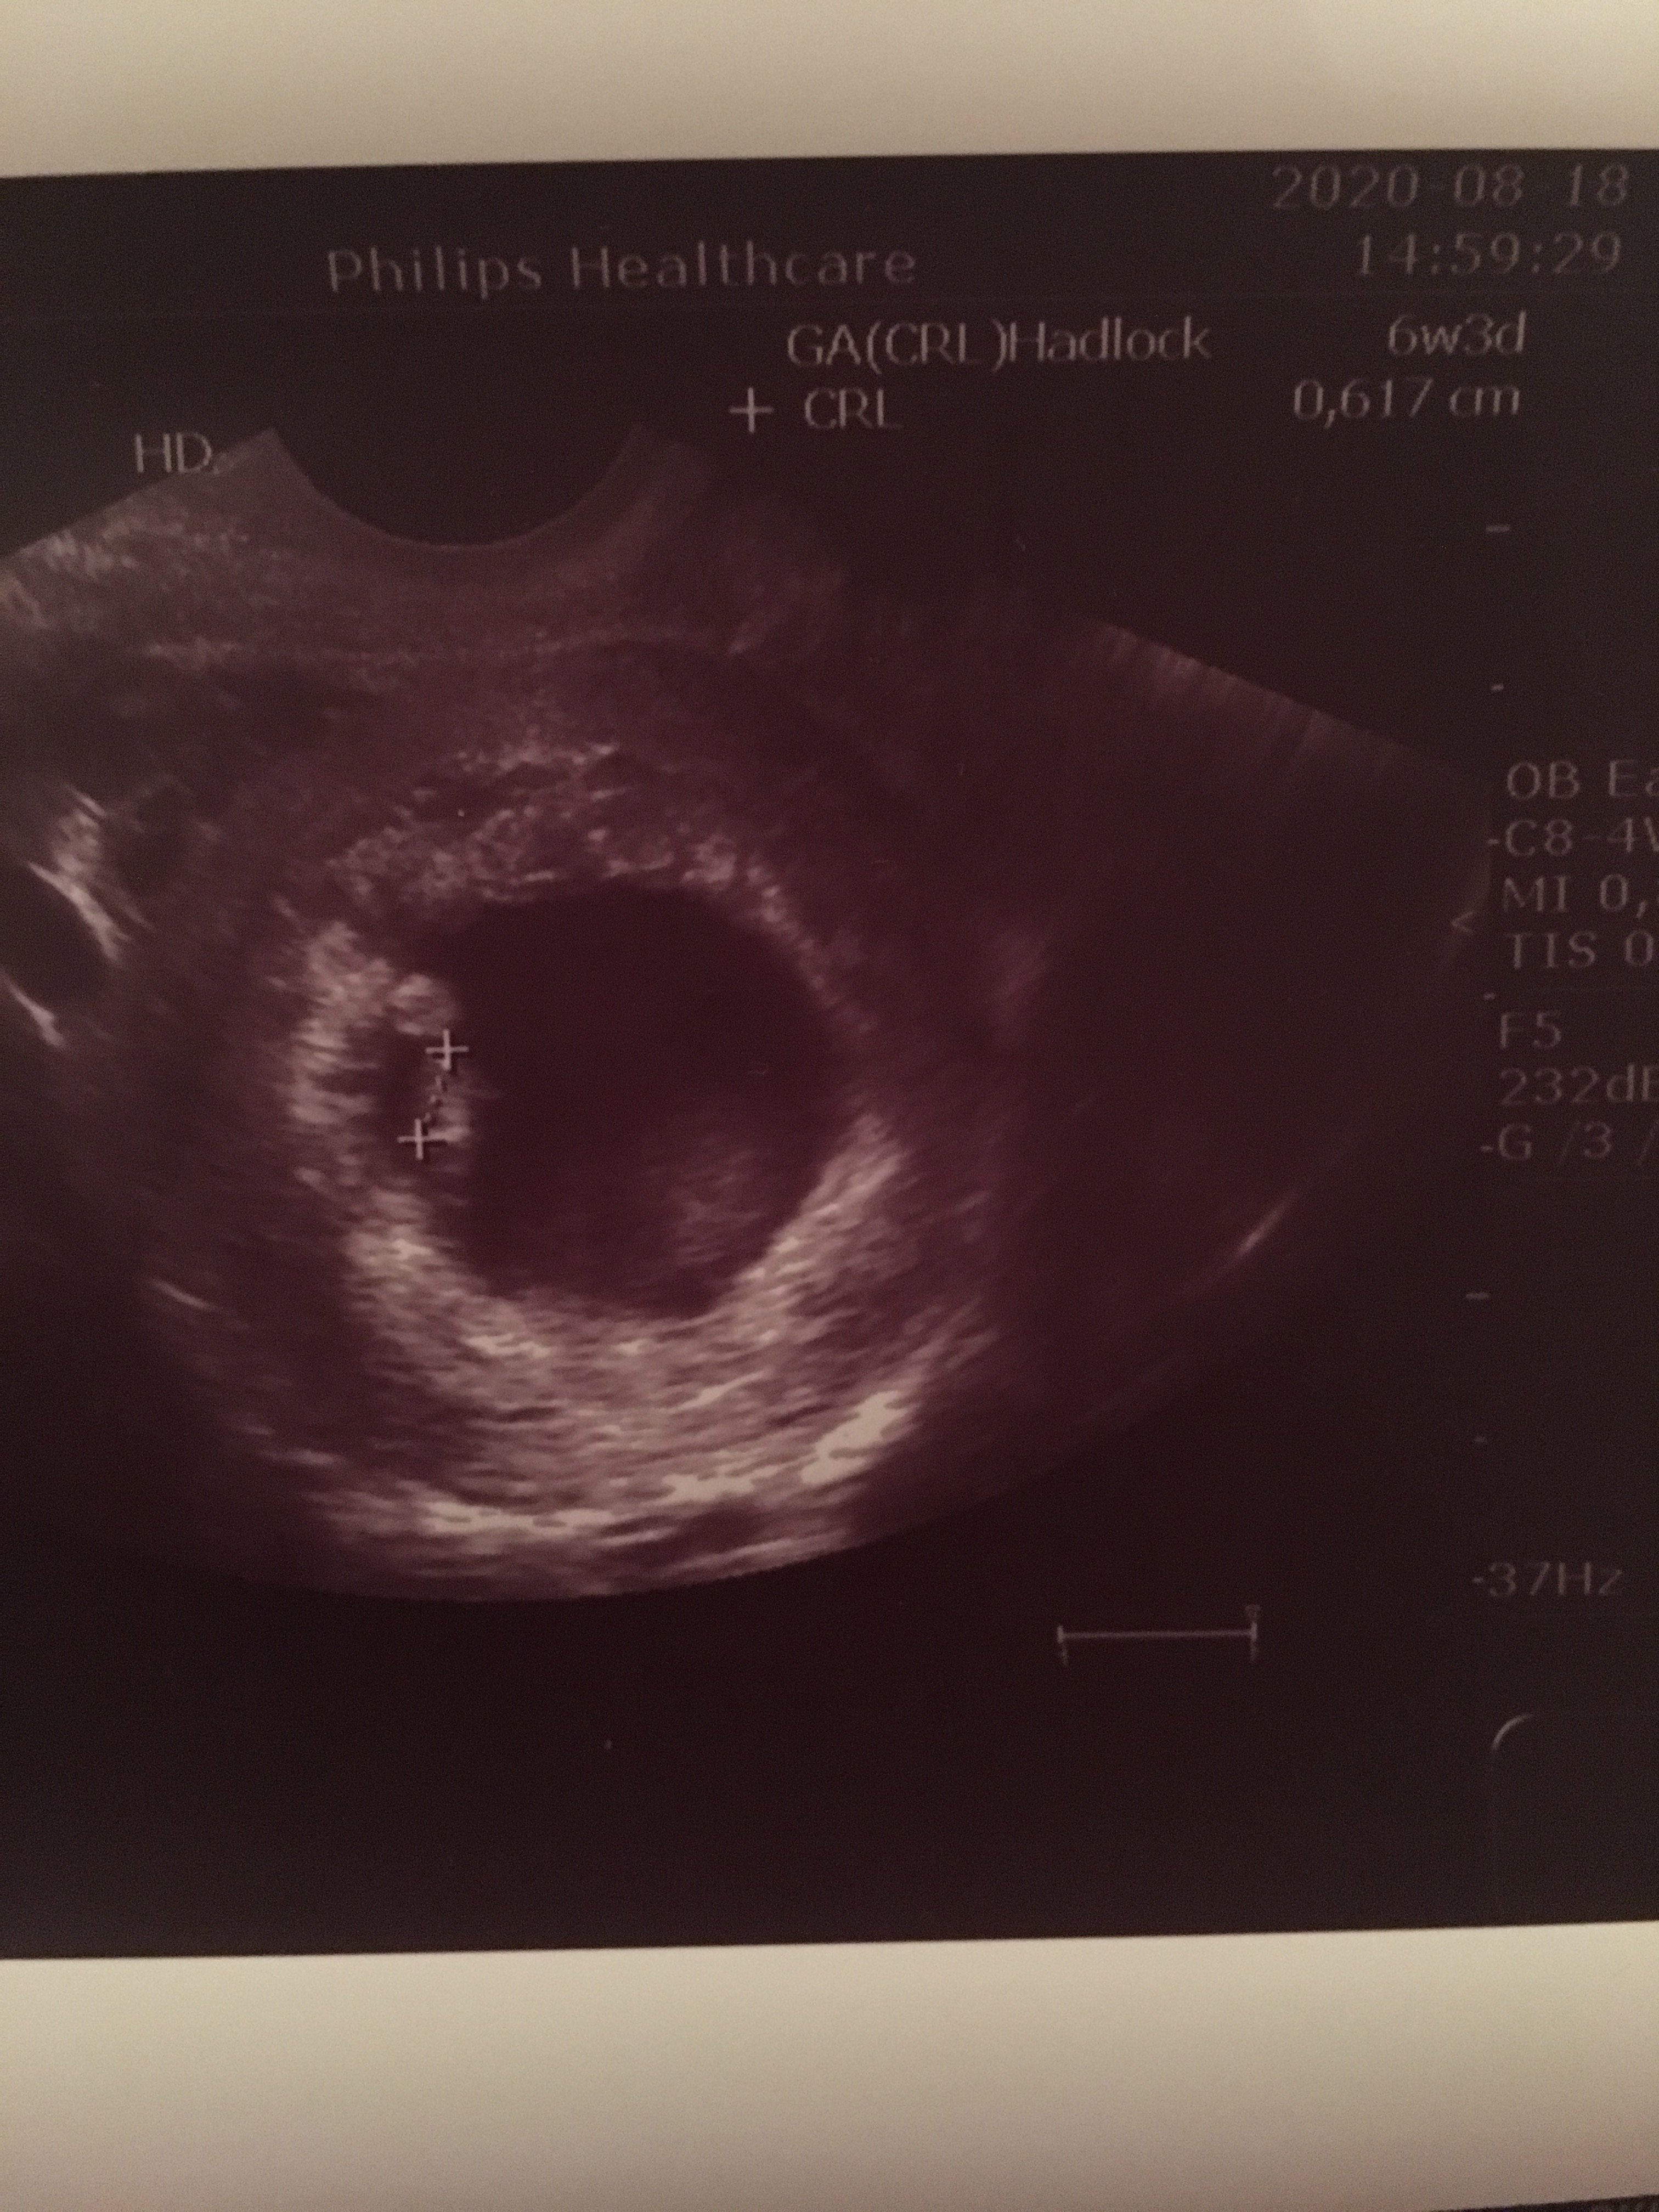

No aż zdjęcie z usg wyciągnęłam: Zobacz załącznik 1165336

0,5 cm, u mnie tez wkradł się babol 😁, 6. tydzień ciąży –

W tym okresie dziecko wymiarami przypomina ziarenko soczewicy – mierzy ok. 5 mm. Mimo tak niewielkich rozmiarów rozwija się już bijące serce o wielkości ziarnka maku.

Pod koniec 7. tygodnia płód zwiększa swoją wielkość nawet ponad dwukrotnie. Dorasta nawet do 12 mm.